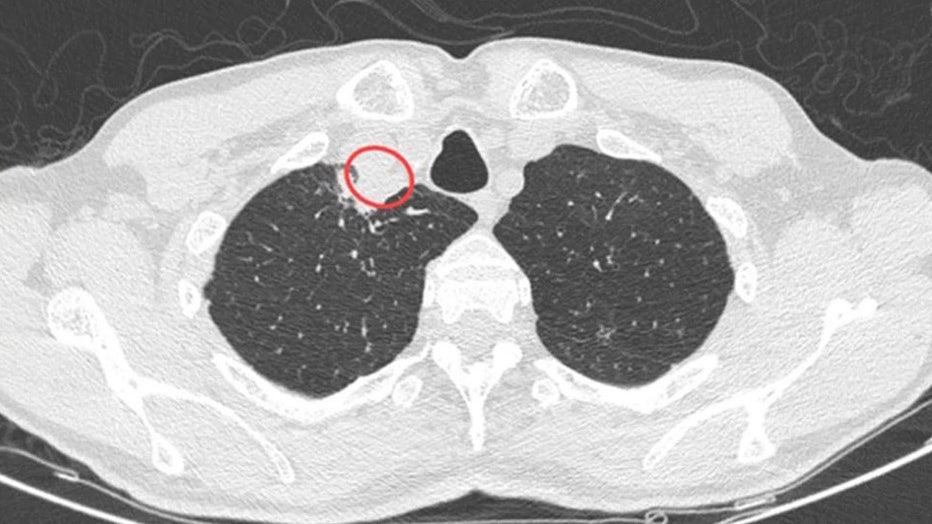

Plant-fungus-III.jpg

CT scan demonstrated the presence of a right paratracheal abscess (Soma Dutta, Ujjwayini Ray)